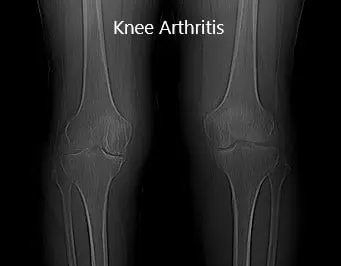

Imaging revealed severe bilateral Osteoarthritis of the knee. The patient was symptomatic mainly in the right knee, he was advised a custom total knee replacement. Risks, benefits and potential complications were all discussed with the patient in detail. He was highly motivated to get back to his baseline and opted for custom total arthroplasty.

Preoperative X-ray showing AP view of the bilateral knee joints.